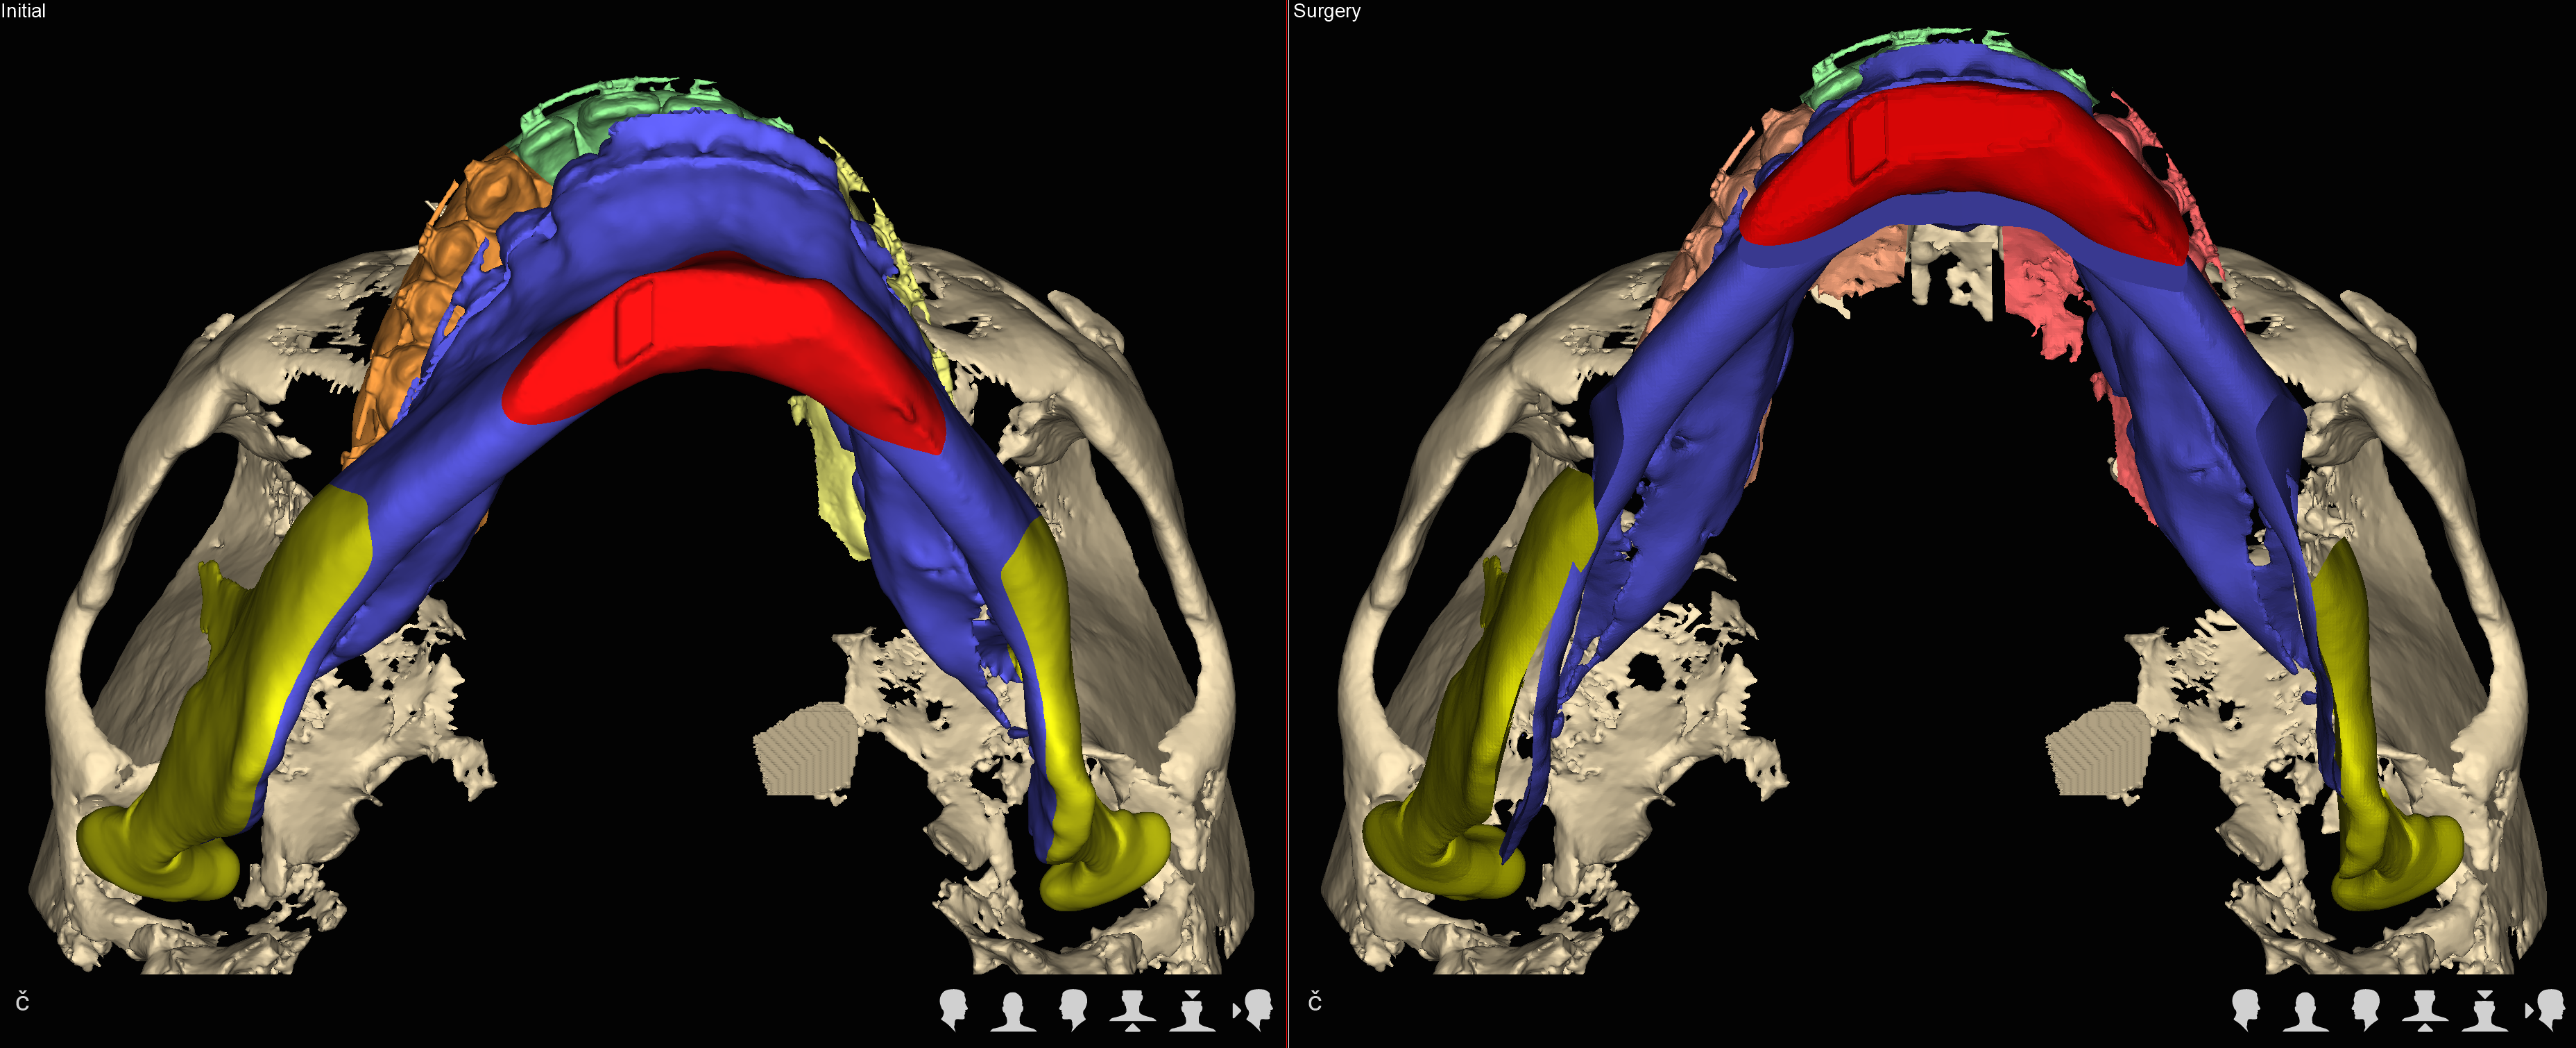

Trójwymiarowe planowanie leczenia wad zgryzu

Nie wyobrażamy sobie planowania operacji wady zgyzu inaczej niż w środowisku 3D.

We współczesnej chirurgii ortognatycznej uzyskanie prawidłowych warunków okluzyjnych czyli prawidłowego zgryzu jest jednym z celów leczenia równie istotnych jak zachowanie prawidłowych stosunków objętościowych w drogach oddechowych czy uzyskanie optymalnej estetyki twarzy.

Jedną z najistotniejszych części leczenia interdyscyplinarnego pacjentów z wadami szkieletowymi jest właściwe zaplanowanie całego procesu leczenia zarówno pod względem przesunięć zębów jak też zmian w układzie kostnym.

Szkielet czaszki twarzowej jest bryłą przestrzenną i rozpatrywanie jego nieprawidłowości w układzie trójwymiarowym pozwala na prawidłowe ich zdiagnozowanie a tym samym na optymalne zaplanowanie przesunięć kostnych, uzyskanie właściwych proporcji twarzy.

W naszym Centrum wykorzystujemy koncepceję FAB (FaceAirwayBite) opracowaną przez Williama Arnetta – światowej sławy chirurga zajmującego się leczeniem wad zgryzu.

U każdego Pacjenta rozpoczynającego leczenie w naszym Centrum po wykonaniu badań diagnostycznych przeprowadzamy szczegółowe analizy dotyczące wzajemnych relacji kostnych w obrębie twarzy, ustawienia zębów, projekcji tkanek miękkich i estetyki twarzy.

Następnie rekomendujemy lub wdrażamy postępowanie ortodontyczne. Po jego zakończeniu przystępujemy ponownie do analiz wszystkich parametrów w obrębie twarzy i przygotowujemy plan leczenia chirurgicznego obejmjący przesunięcia kostne z zakresie układu szkieletowego z uwględnieniem koncepcji FAB.

Docelowo efektem jest wydruk szablonów chirurgicznych na drukarce 3D.

W trakcie planowania powstają rownież symulacje efektów leczenia (symulacje a więc nie gwarantowany efekt), które są przedstawiane pacjentowi przed wykonaniem zabiegu.